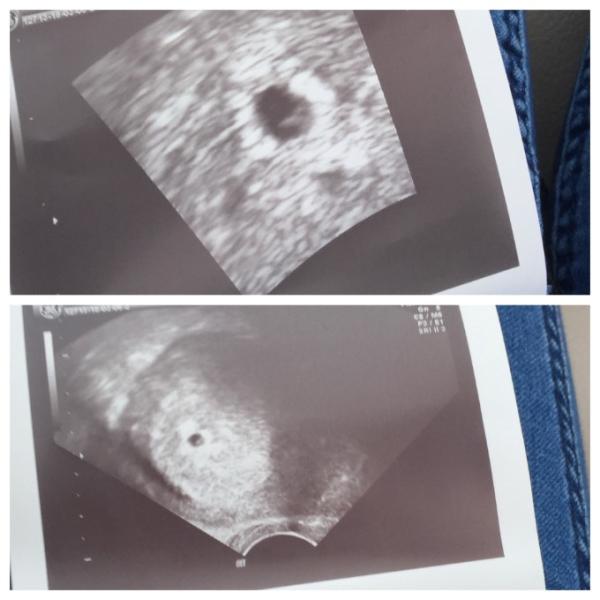

Hallo meine lieben Solangsam fange ich an zu realisieren das ich wirklich schwanger bin. Bin wohl laut Arzt 5+4 und man hat heute was im Ultraschal gesehen Fruchthöhle und Dottersack. Ich hoffe das ich nächste Woche das Herzchen schlagen seh ... hab aber noch totale Panik und Angst das was schief laufen könnte :-( ich bete zum lieben Gott das mich mein kleiner Schatz nicht verlässt. Soweit alles gut läuft war dies auch mein letzter Eintrag hier. Ihr wart toll und ich bin froh das es so austausch Foren gibt. Danke ! Ich wünsch euch alles Glück der Welt und ganz viel Positiv Ergebnisse !!!!!

Bild zu Unglaublich < 3 Ultraschal - Kinderwunschbehandlung